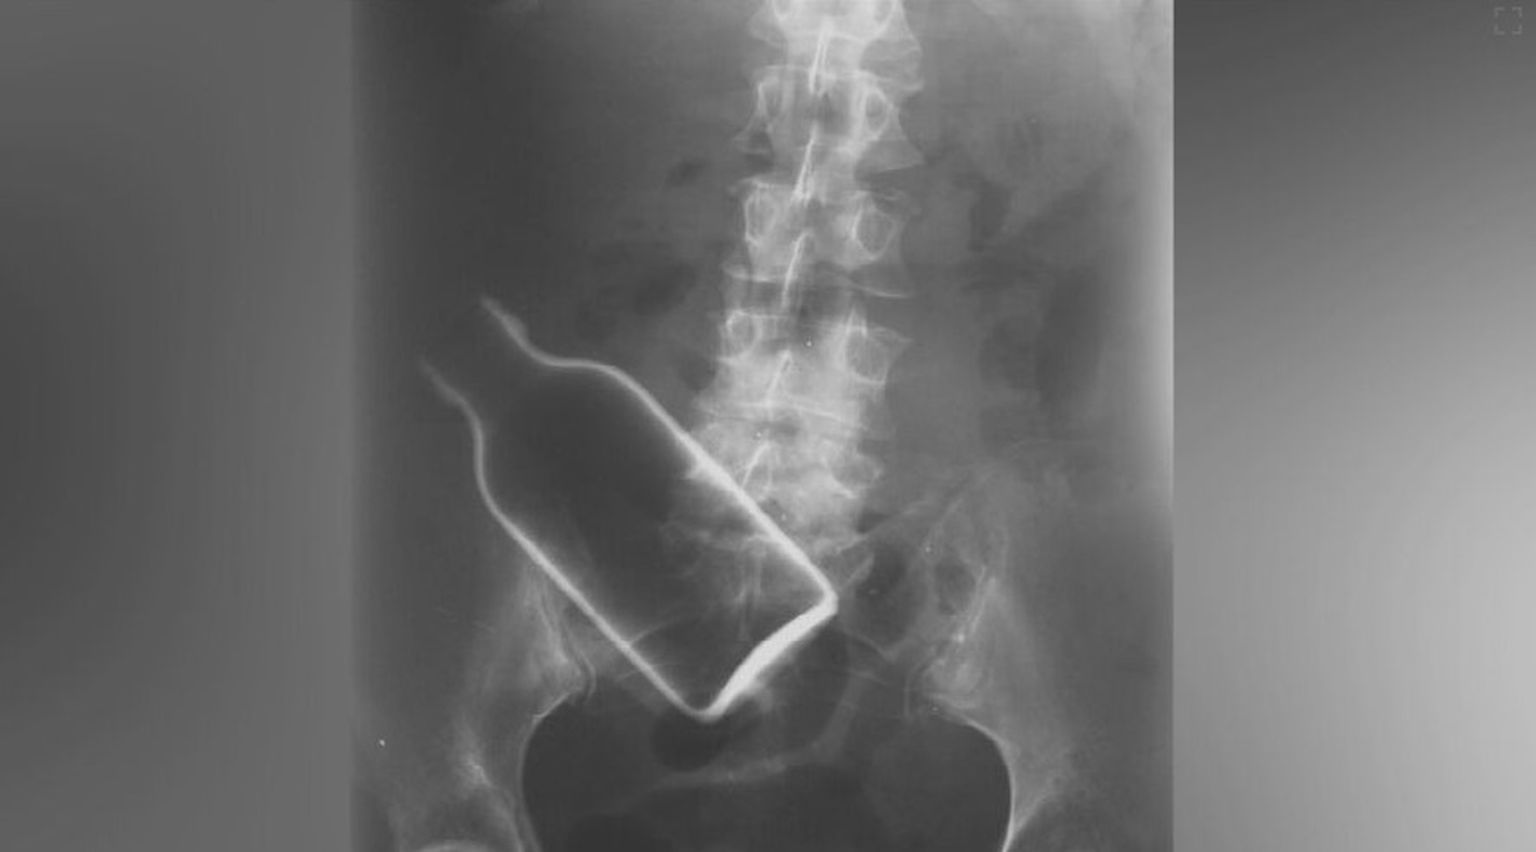

• Strano tijelo u tijelu, ilustracija - 1 Foto: DNEVNIK.hr

• Strano tijelo u tijelu, ilustracija - 2 Foto: DNEVNIK.hr

• Strano tijelo u tijelu, ilustracija - 3 Foto: DNEVNIK.hr

• Strano tijelo u tijelu, ilustracija - 4 Foto: DNEVNIK.hr

• Strano tijelo u tijelu, ilustracija - 5 Foto: DNEVNIK.hr